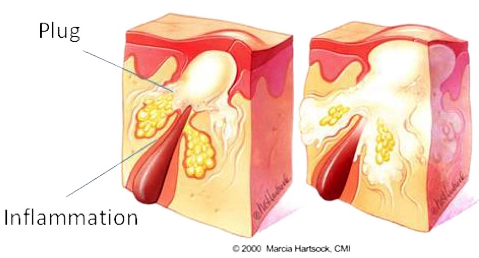

Delving beneath the skin's surface, we find a complex network of hair follicles intertwined with sebaceous glands. These glands make sebum, a natural oil that keeps our skin moisturised and supple.

However, various factors including hormonal changes, stress, and medications can stimulate these glands to induce excess sebaceous activity. When too much oil mixes with dead skin, it blocks pores and provides an ideal environment for bacteria to proliferate and the formation of acne symptoms.

Papules & Pustules

Papules are small red, solid, and inflamed bumps on the skin that do not contain pus.

Pustules are infected papules that have accumulated pus, white or yellow, from bacterial activity.

Both are a result of from pores becoming clogged with oil and dead skin cells.